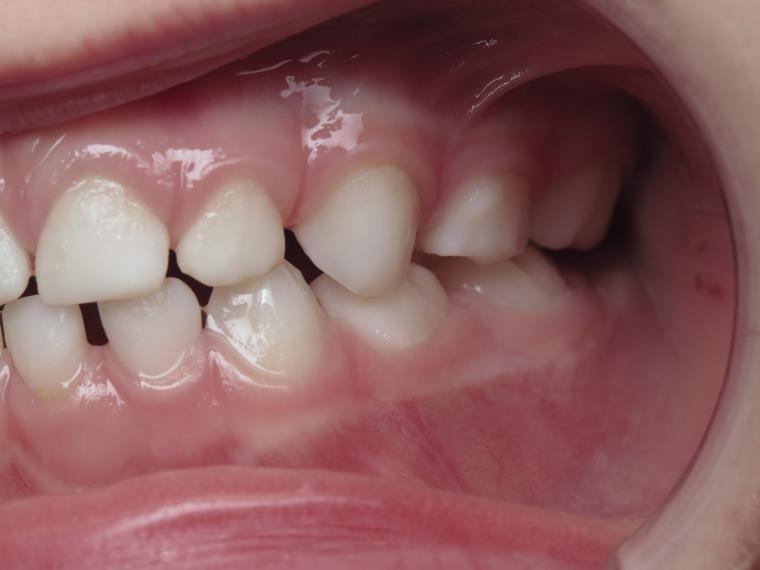

inversion des dents postérieur coté droit